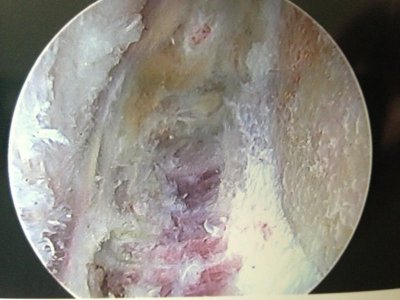

Here are the after photos. Everything is cleaned up pretty good now.